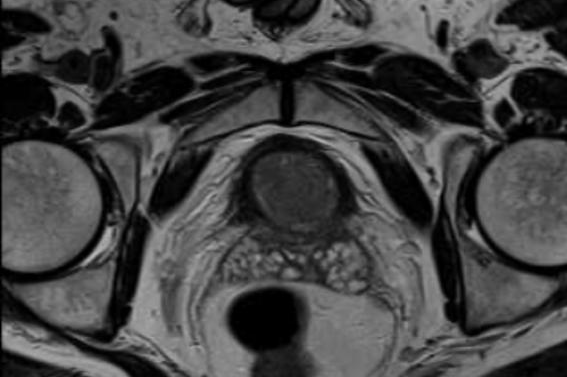

今年初,张先生了解到贵州航天医院泌尿外科相关男科信息,遂前来就诊,完善MRI(磁共振)等检查后,发现左侧精囊内存在结石并伴有炎症。泌尿外科专家团队对此进行了深入讨论,结合患者身体情况排除了相关手术禁忌,征得患者及家属同意后,决定采用精囊镜手术治疗方案。

术中,李国成副主任医师通过细如笔芯的精囊镜,见患者射精管开口喷血,左侧精囊内结石,双侧精囊内黏膜有慢性炎症改变。最终,在精囊镜的导引下,精准定位结石,同步进行冲洗、取石和止血等操作,成功完成手术。

射精管出血

精囊内结石

炎症改变